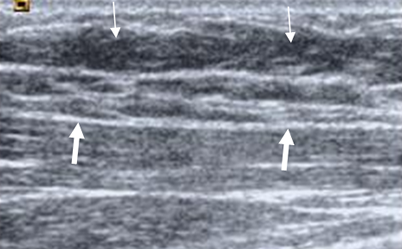

En la ecografía se identifica el tejido celular subcutáneo, compuesto por tejido adiposo hipoecoico. Por debajo se ubican las fibras musculares, con el epimisio y perimisio. (Ver valoración radiológica de las lesiones musculares). (Fig 4 y 5).

Esta modalidad permite identificar colección de tejidos blandos y presencia de derrame articular. Igualmente sirve de guía para el drenaje percutáneo de colecciones, realizar punciones articulares o toma de muestra para estudio bacteriológico.

Fig 4. Tejido celular subcutáneo normal.

Ecografía. Tejido celular subcutáneo hipoecoico. (Flechas delgadas). Está separado del músculo por la fascia, que se aprecia como imagen lineal e hipercoica. (Flecha gruesa).